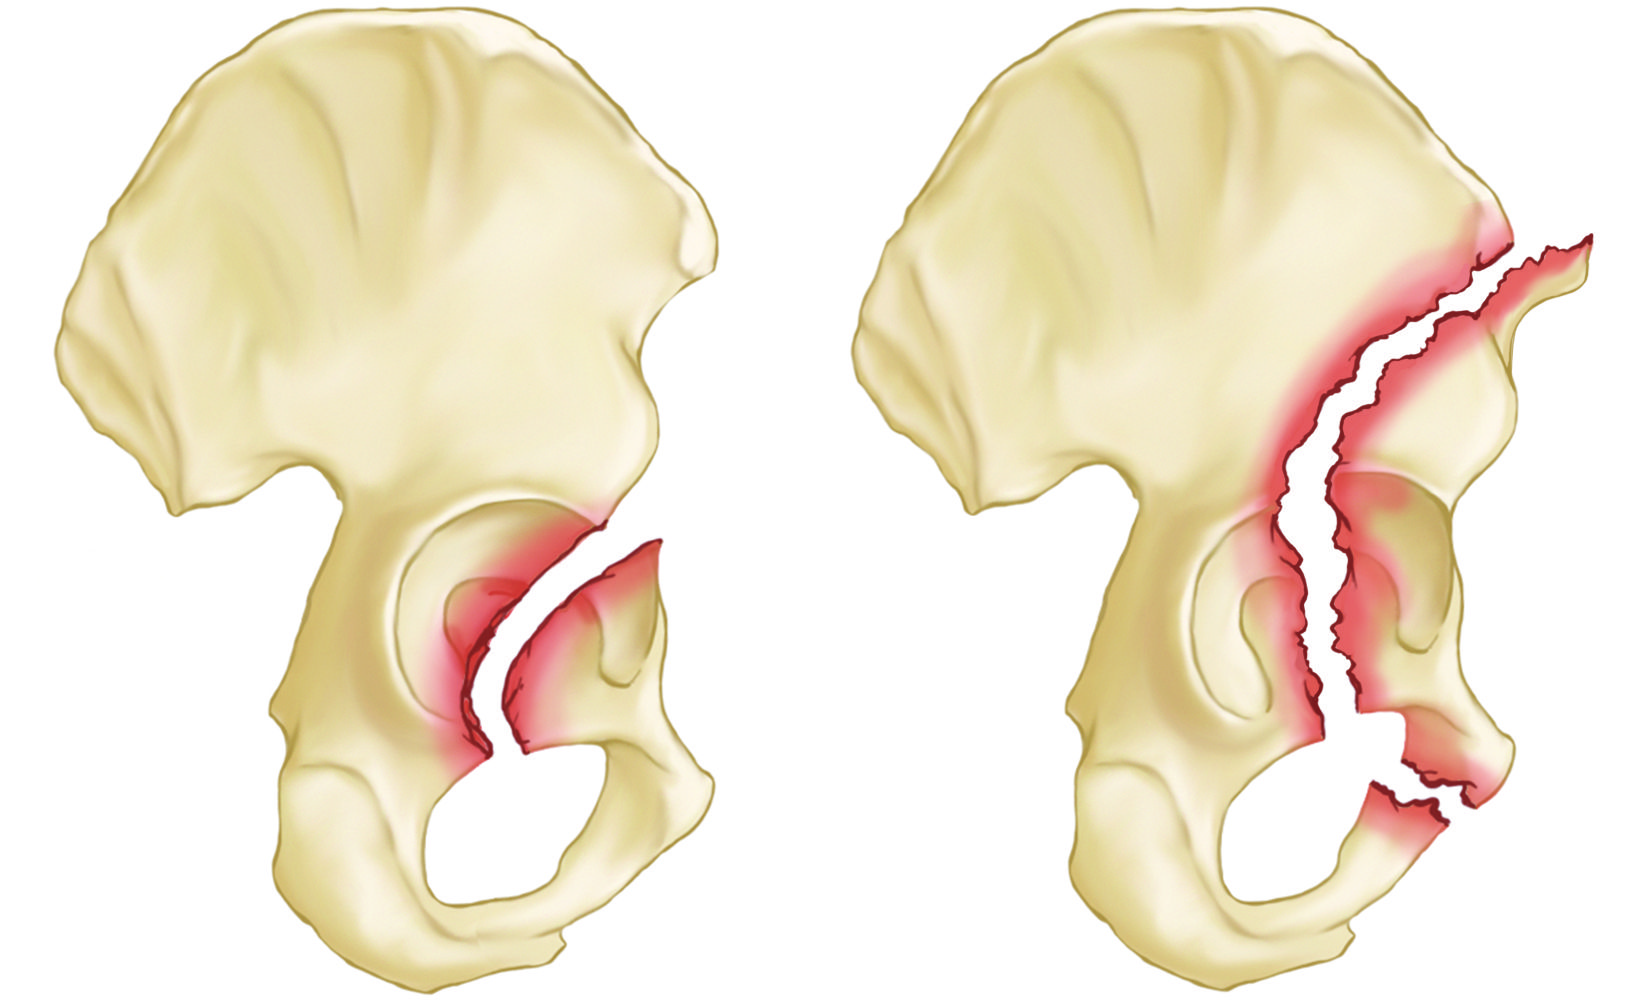

Common acetabular fracture patterns include:

Anterior wall and anterior column acetabulum fractures

(Left) Anterior wall fracture

(Right) Anterior column fracture

Posterior wall and posterior column acetabulum fractures

(Left) Posterior wall fracture

(Right) Posterior column fracture

Transverse and T-shaped acetabulum fractures

(Left) Posterior wall transverse (across) fracture (Right) T-shaped fracture